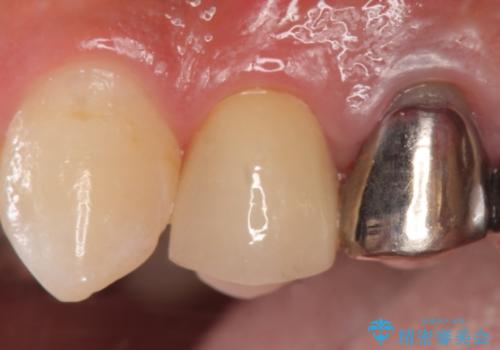

そのため左上4番目の歯は根管治療を行い、歯茎の膿の出口の消失を確認後、オールセラミッククラウンによる補綴を行いました。

今回用いたオールセラミッククラウンはジルコニアフレームという白い素材の上にセラミックを盛っているため、審美性が非常に高いのが特徴です。

また、ジルコニアは人工ダイヤモンドの材料にも使われているほど高い強度を持っており、そのためオールセラミッククラウンは審美性だけでなく、奥歯やブリッジの補綴も可能とするクラウンです。